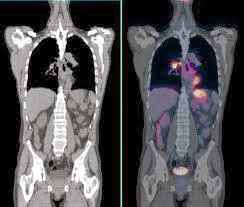

• Sistema PET/TC

Sistema PET/TC

Surge la tomografía por emisión de positrones que utiliza pequeñas cantidades de materiales radioactivos denominados radiosondas o radiofármacos, una cámara especial y una computadora para evaluar las funciones de tejidos y órganos.